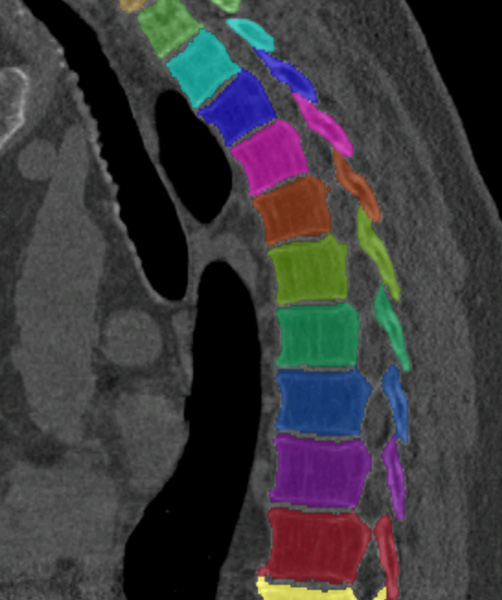

5.1 Segmentation performance

Similar performance was achieved for vertebra segmentation in various CT datasets with an average Dice score of and for vertebral body segmentation in an MR dataset with an average Dice score of . Surface distances were lower on CT images compared to MR images ( vs. ), however, there were also fewer training scans available in the MR dataset. Figure 4 illustrates the magnitude of differences of the automatic segmentations from the ground truth segmentations.

(a) Low-dose chest CT

(b) Lumbar spine CT (xVertSeg.v1 dataset)

(c) Lumbar spine MR

In the CT datasets, the segmentation was more accurate on high-resolution dedicated spine scans of healthy subjects compared with low-dose low-resolution chest CT scans and scans of subjects with in some cases severe compression fractures. This is also visible in the segmentation performance stratified by vertebra (Figure 5). Segmentations were more accurate for the lumbar (L1-L5) than for the thoracic vertebrae (T1-T12), which are covered by the more challenging low-dose chest CT scans. Outliers among the lumbar vertebrae correspond to vertebrae from the xVertSeg.v1 dataset, which features a number of severely deformed lumbar vertebrae that are particularly challenging to segment.

In comparison with other vertebra segmentation methods, our iterative instance segmentation approach outperformed previous methods on the thoracolumbar spine CT dataset as well as on the lumbar spine CT dataset. In both cases, there was a substantial improvement in average Dice score and especially also in the surface distance (Table 1). On the xVertSeg.v1 dataset with various fractured vertebrae, our method performed comparable to the method of Sekuboyina et al. (2017) and not as well as the method of Janssens et al. (2018). However, both of these publications used a different separation between training and evaluation data and the results are therefore not directly comparable. For vertebral body segmentation in MR, our approach achieved on average higher Dice scores and lower surface distances than previous methods, but with higher variance compared to Korez et al. (2016). Although the automatic segmentation was overall accurate on low-dose chest CT, the performance was still slightly below the level of interobserver variation (average difference of in Dice score and in surface distance).